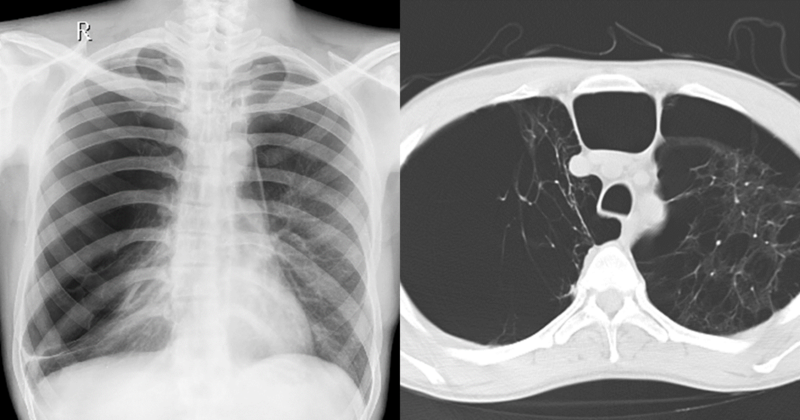

CXR and HRCT showing giant bulla and diffuse emphysema

Surgery in COPD